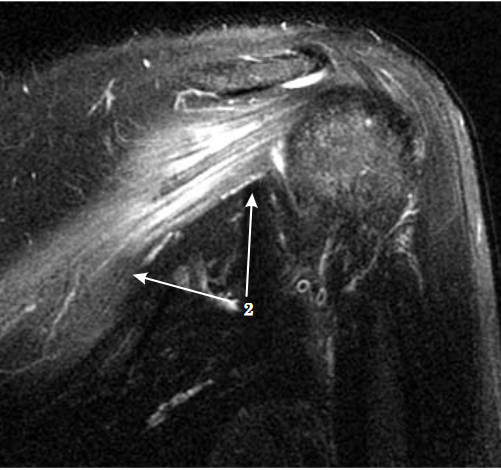

- Resonancia magnética: Cuando se sospeche de otra causa potencial (neoplasia, hernia cervical…) y nos puede mostrar si se realiza el estudio sobre la musculatura afectada. Mostrando patrones de edema difuso en fases iniciales y el aumento de infiltración grasa intramuscular en fase tardía.

Imágenes de este caso clínico

- Cosme LJ, Vivas BI, Roldán VE, et al. Síndrome de Parsonage-Turner y su evaluación por resonancia magnética: Presentación de un caso. Med Sur. 2009;16(1):31-34.